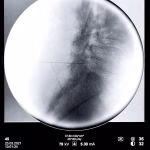

- Rizotomia percutânea lombar

- Implante de neuroestimulador medular

- Bloqueios anestésicos